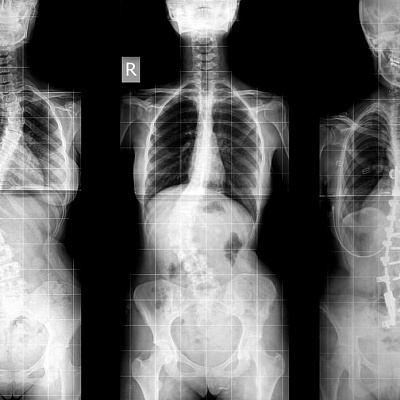

Инструментальная диагностика проводится, чтобы получить больше информации. Показаны:

- рентгенография в нескольких проекциях: рентген при искривлении позвоночника — важное исследование, которое проводится первым;

- томография (МРТ, КТ).